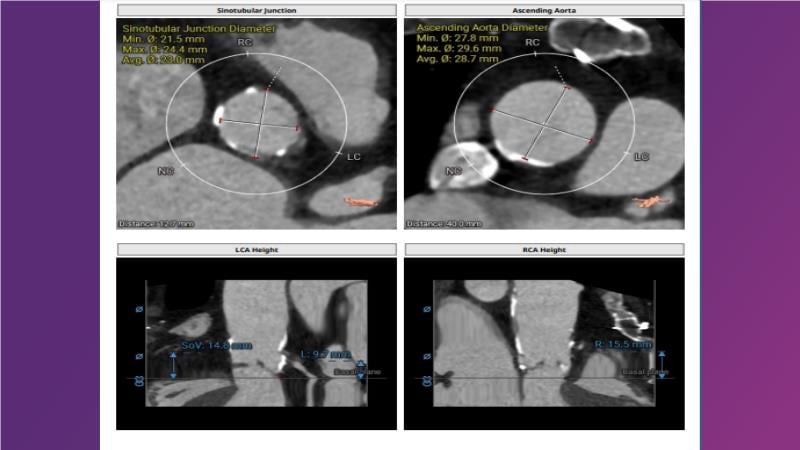

Gain expertise in selecting the appropriate TAVI device for achieving stable deployment in a 90-degree horizontal aorta. Discover techniques for ensuring smooth deliverability, particularly when navigating through tight and tortuous anatomies. Additionally, learn strategies to prepare for future coronary access, irrespective of the height of the left or right coronaries.

• To learn how to select your TAVI device in order to achieve stable deployment in 90 degrees horizontal aorta

• To be ready for future coronary access regardless of the height of left or right coronaries